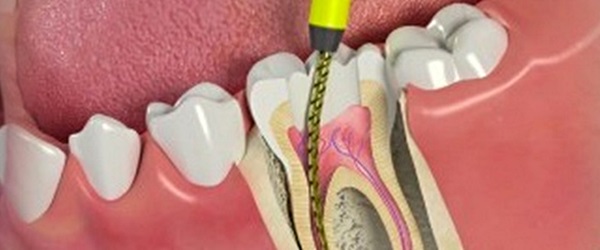

Root Canal Treatment (RCT)